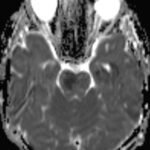

There is a growing body of literature and scientific discovery on pediatric autoimmune encephalitides. This is a heterogenous group of neuroinflammatory conditions leading to often perplexing acute and progressive neurologic and/or neuropsychiatric symptoms. This report demonstrates the evaluation and management of an adolescent with myelin-oligodendrocyte glycoprotein (MOG) antibody-associated fulminant acute disseminated encephalomyelitis (ADEM) in the context of current literature. The featured magnetic resonance imaging uniquely highlights progressive central nervous system lesions detected over the course of the first week of disease.